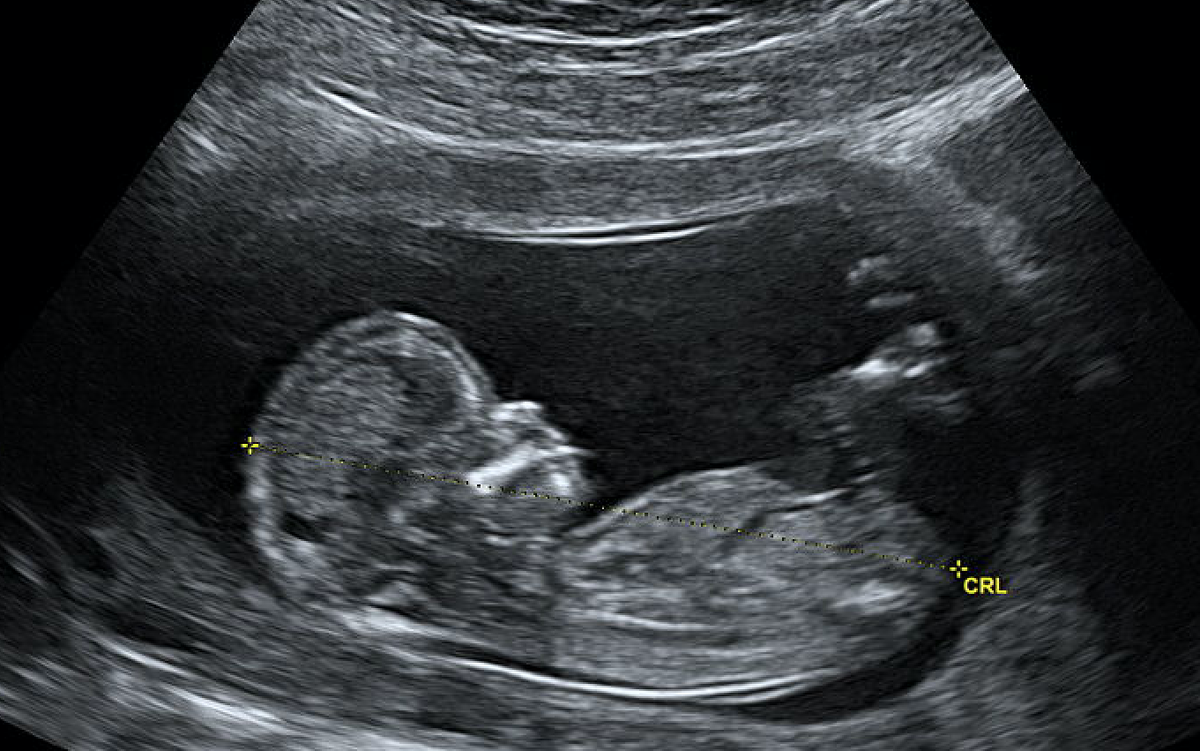

«Насть, у меня для тебя не очень хорошие новости», - сказала мне моя врач-гинеколог на очередном приеме. «Пришли результаты скрининга. У тебя высокий риск синдрома Дауна» У меня подкосились ноги. Как так? На УЗИ все было хорошо, без патологий, какой риск?!

В общем, врач посоветовала мне не переживать раньше времени, сказав, что сейчас почти каждой второй беременной ставят такой риск и он не подтверждается. На этом же приеме она еще раз сделала УЗИ и не обнаружила никаких отклонений, что немного меня успокоило. Но, все же, направила меня к генетику. Итак, я на приеме у генетика – самого лучшего в нашем городе Все в отзывах ее нахваливали. Но мне она сразу не понравилась.

Очень небольшой, но есть. А я не хотела рисковать. Я чувствовала и верила, что с моей дочкой все хорошо. Ведь, по УЗИ все было отлично.

О своем решении я сказала своему врачу. Почти каждый прием врач делала мне УЗИ, чтобы убедиться, что никаких видимых аномалий у моего ребенка нет.